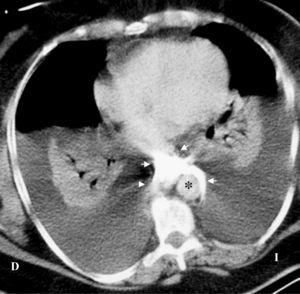

Al ingreso, la paciente estaba sedada y conectada a ventilación mecánica. Su temperatura era de 35,7º C, la frecuencia cardíaca de 140 latidos por minuto (lat/min), la presión arterial sistólica de 70 mmHg y la presión venosa central (medida por el CVC yugular) de 20 mmHg. Presentaba cianosis central y edemas en cara y cuello. La exploración cardiopulmonar puso de manifiesto tonos cardíacos fuertes, murmullo vesicular disminuido y matidez en la percusión del tórax. No se determinó la existencia de pulso paradójico. Los principales datos analíticos fueron: hemoglobina 11,3 g/dl, plaquetas 191 miles/µl, leucocitos 21,8 miles/µl con 94% de polimorfonucleares, proteínas totales 4,6 g/dl, creatinina 1,4 mg/dl y glucosa 376 mg/dl. Los gases arteriales fueron (FiO2 1): pH 7,19, PaO2 74 mmHg, PaCO2 35 mmHg, y bicarbonato 14,2 mmol/l. El electrocardiograma (ECG) reveló taquicardia sinusal a 130 lat/min y un patrón rSr' en derivación V1. La radiografía de tórax mostró un ensanchamiento mediastínico, derrame pleural bilateral y posición anómala de la punta del CVC en la línea media del mediastino. Puesto que fue imposible aspirar sangre o fluidos por el catéter yugular, se paró la infusión de fluidos. La presión venosa central, registrada a través de un nuevo CVC colocado correctamente en la vena subclavia izquierda, también midió 20 mmHg. Una infusión de dopamina a 15 µ/kg/minuto sólo logró incrementar la presión arterial a 95/70 mmHg. Un ecocardiograma transtorácico reveló unos ventrículos hipercontráctiles y ausencia de derrame pericárdico o pleural comprimiendo el corazón. Se realizó una tomografía computarizada del tórax (fig. 1) que mostró extravasación mediastínica del contraste radiológico inyectado a través del CVC yugular y derrames pleurales masivos con atelectasia por compresión de ambos pulmones. El CVC yugular fue retirado y se colocaron dos tubos de tórax que drenaron 3.750 ml de líquido serosanguinolento. Treinta minutos después del drenaje, la presión arterial subió a 140/70 mmHg, la presión venosa central descendió a 7 mmHg y la PaO2 se incrementó a 107 mmHg (FiO2 0,4). Seis horas más tarde, la paciente pudo ser extubada y dada de alta de la Unidad de Cuidados Intensivos (UCI) un día después.

Figura 1. La tomografía computarizada de tórax, obtenida tras la inyección de contraste a través del catéter yugular, demuestra extravasación mediastínica del contraste (flechas blancas) y derrames pleurales bilaterales con marcado colapso pulmonar. Notese el contraste mediastínico alrededor de la aorta (*).